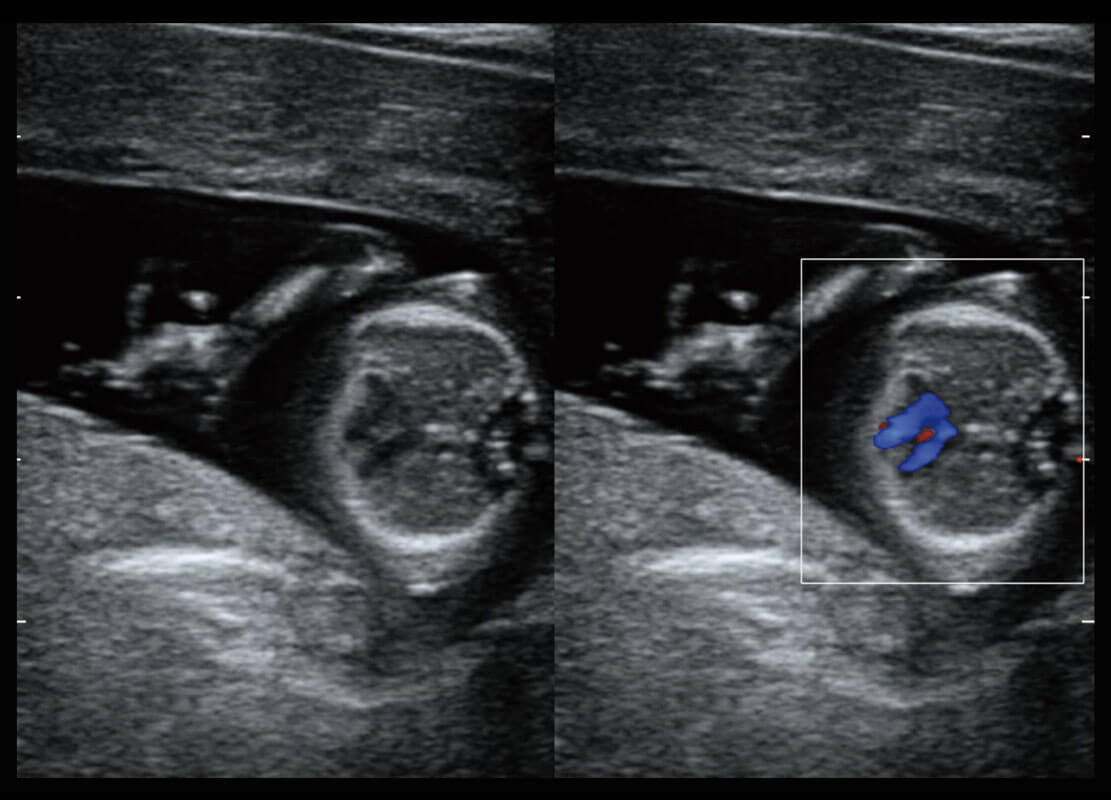

胎心筛查

P60搭载一系列胎儿心脏成像技术,实现精细的胎儿心脏评估。

• 四腔切面

• 四腔心血流

• 右室双出口

• 胎心容积成像